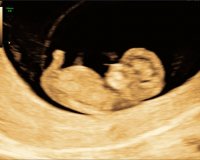

Så fine bilder!Må bare dele disse to bildene fra TUL som vi var på 1.DesemberLille knøttet lå å sprellet med føttene og hendene, og kosa med den ene hånda i fjeset sitt

Ah! Jeg skal på TUL når jeg er 11+3. Kjekt å vite at man får så fine bilder så tidligJeg trodde jeg var 10+0 på vei den 1.Desember, men jordmor som utførte TUL mente jeg var 10+3 grunnet størrelsen på babyen , så nå avventer vi til vi skal på OUL for å vite om vi får termin i slutten av juni eller starten av juli.

Det forstår jeg veldig godt! Var heller ikke på TUL med min første, så måte nå! Tiden før magen vokser/man kjenner liv er jo ikke den letteste akkurat, så er veldig godt med bekreftelseJa det var helt fasinerende å se på at et lite knøtt på 3,5cm lå å sprellet, ble pluttselig så mye mer virkeligvar ikke på TUL med førstefødte for 10år siden men veeeldig glad for at vi dro på det nå